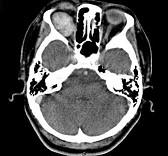

问题 41岁女性,右眼胀痛、眼球外突3月余,体检,发现低头时右侧眼球外突加重,CT检查如图所示,请选择最可能诊断()

选项 A.右侧眶内血管瘤 B.右侧眶内炎性假瘤 C.眼型格氏病 D.右侧眶内神经鞘瘤 E.右侧眶内皮样囊肿

答案 A